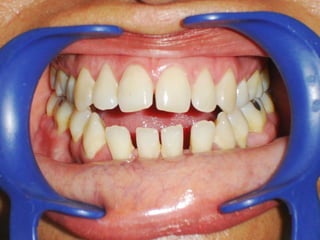

La paciente muestra una franca disgnatia, clínicamente

observamos malposición dentaria secundaria a la falta de

armonía máxilomandibular.

Marcada Clase III

Hábito Lingual

Sobremordida horizontal: –1.5 mm

Sobremordida vertical: + 1 mm.

Frente:

Línea media desviada

Mordida cruzada anterior

Arcada Inferior:

Forma ovalada

Colapso posterior

Ligero apiñamiento de anteriores

Rotación de premolares